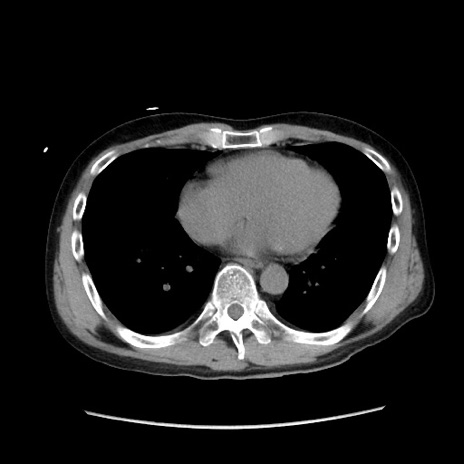

症例37(横断像)

【症例】40歳代 男性

【主訴】腹痛

【現病歴】4時間ほど前に電車に乗車中に臍部上より腹痛出現。徐々に増悪し起立困難となり、救急外来受診。生ものは数日食べていない。今朝お雑煮を食べた。

【身体所見】BT 36.8℃、BP 117/84mmHg、HR 91/min、SpO2 97%、苦悶様、腹部:臍上部広範囲圧痛あり、反跳痛±

【データ】WBC 8100、CRP 0.03